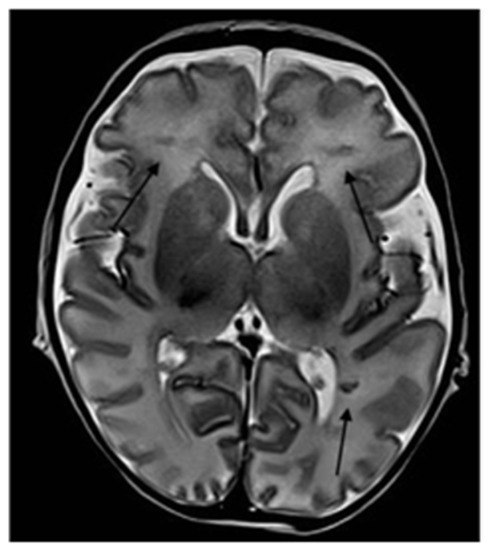

2. Case Description